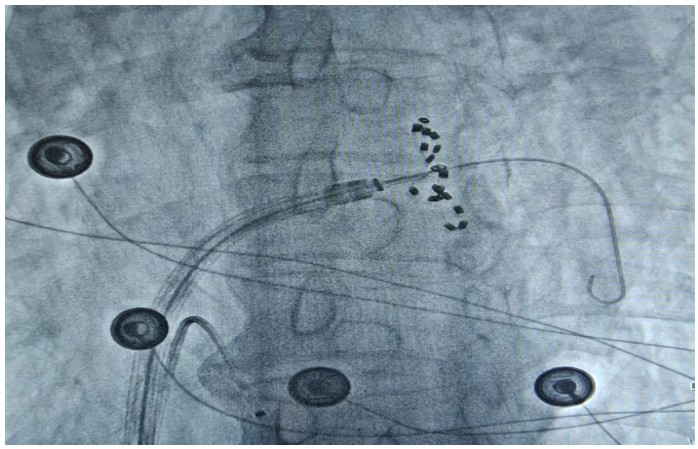

通訊員何紅丹報(bào)道:2025年1月17日,衡陽(yáng)市中心醫(yī)院心血管內(nèi)科趙慶禧主任醫(yī)師團(tuán)隊(duì)與心血管內(nèi)科電生理團(tuán)隊(duì)協(xié)作,在全麻下成功為一名72歲的男性患者實(shí)施了陣發(fā)性房顫FARAPULSE脈沖電場(chǎng)消融手術(shù)。此次手術(shù)為目前全球最先進(jìn)的PFA消融導(dǎo)管上市后全國(guó)首批臨床應(yīng)用,在湘南地區(qū)首次開展,能更精準(zhǔn)地作用于目標(biāo)區(qū)域,減少對(duì)周圍組織的損傷,極大程度降低并發(fā)癥的發(fā)生,具有更高的安全性。

趙慶禧介紹,房顫是常見(jiàn)于老年人的心臟問(wèn)題,通俗的講就是心臟“亂跳”。發(fā)生房顫時(shí)患者心慌心悸難忍,極易誘發(fā)腦卒中等惡性后果,嚴(yán)重危害生命健康。目前,房顫的治療方法包括藥物治療和傳統(tǒng)導(dǎo)管消融。相較于藥物治療和傳統(tǒng)導(dǎo)管消融,脈沖電場(chǎng)消融可選擇性的損傷心肌,而保留血管、神經(jīng)及心臟周圍組織。更快的消融脈沖電場(chǎng)消融(PFA)技術(shù)是最新的消融技術(shù),它能通過(guò)高壓電脈沖,實(shí)現(xiàn)消融點(diǎn)細(xì)胞凋亡的目的,達(dá)到抑制紊亂心律發(fā)生的作用。與傳統(tǒng)消融技術(shù)相比,脈沖電場(chǎng)消融具有更高的組織選擇性、更快的消融速度以及更低的貼靠要求,成為臨床迫切需要的突破性創(chuàng)新治療方法,為患者帶來(lái)了新的選擇和新的希望。